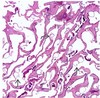

You are called by the neurology team to perform a skin biopsy for the workup of cerebral autosomal dominant arteriopathy with subcortical infarcts and leukoencephalopathy. You perform a 4-mm punch biopsy of the arm.

In what medium do you place the specimen?

Cerebral autosomal dominant arteriopathy with subcortical infarcts and leukoencephalopathy (CADASIL) is a neurologic disorder caused by mutations in NOTCH3. Patients with CADASIL have migraines, recurrent strokes, and progressive dementia. Transmission electron microscopy (TEM) of a skin biopsy is the gold standard to detect pathologic findings.

Placing the skin specimen in the correct medium, glutaraldehyde for TEM, is critical for accurate diagnosis.